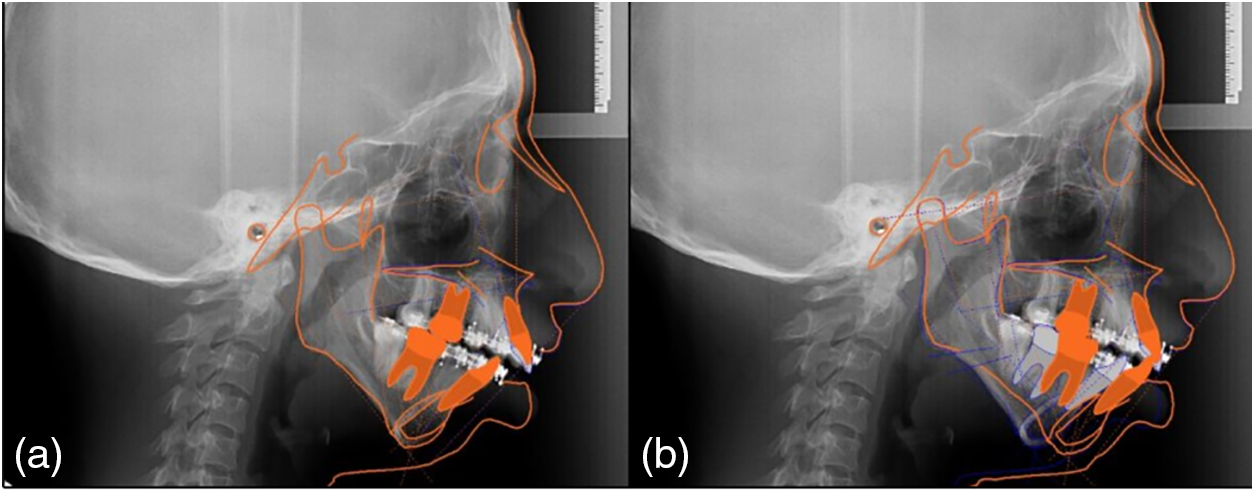

The clinical triad observed in 80% of SMG patients and consanguinity in this case support the diagnosis of this rare autosomal recessive disorder [3]–[5]. A multidisciplinary team including genetics, craniofacial surgery, gastroenterology, nutrition, neurology, otolaryngology, phonology, pediatric dentistry, maxillofacial surgery and orthodontics was formed to treat this patient. In the case of orthodontics and maxillofacial surgery, the goals were focused on improving function and aesthetics. The severe transverse collapse was solved. The airway was improved by palatal expansion. To achieve better and more predictable results, preoperative cephalometric planning was performed (Fig. 2). Preoperative decompensation was achieved using an articulating device (Fig. 6). Furthermore, the facial profile was improved using advanced mentoplasty (Figs. 5, 7). Changes in preoperative and postoperative cephalometric measurements are shown in Table II. Significant results were achieved at both the facial and the skeletal levels. The ameloplasty and the bite adjustment provided a canine guide and functional incisors that helped open the airway (Fig. 8). Our results reflect the efficacy of orthodontic treatment and surgical procedures in improving the function and aesthetic appearance of the patient. The need for continued research in this area to improve the understanding and clinical management of this unique population is highlighted by the lack of data on the prevalence of dentofacial disease in patients with GMS [5]. This case report is consistent with those reported in other articles showing the clinical trial of GMS, evidenced by facial and dental features such as mandibular retrognathism, deep palate, dental malocclusion, and dental fusion [10]–[12].

Fig. 7. Superimpositions: a) The facial axis is projected at 10°, b) Point A is intruded (qx), and c) The incisors maintain their inclination and the molar is mesialized.

Fig. 8. Comparison of the airway a) preoperative and b) postoperative.